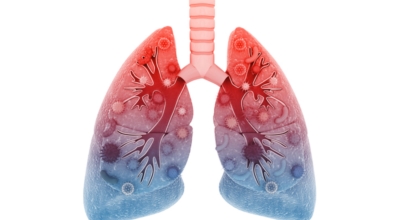

인체가 순조롭게 기능을 발휘하려면 폐 건강이 필수다. 폐는 인체가 효율적으로 움직이는 데 있어 바퀴 안에 있는 톱니 같은 역할을 하기 때문이예요. 산소를 제공하는 폐 기능이 감소하게되면 폐렴이나, 만성 폐쇄성 폐질환(COPD), 천식 등 정도가 심한 호흡기 질환 발생 위험이 증가해요. 이런 질병들은 폐를 공격해 숨쉬기 힘들게 만들어요.

특별히 현대 사회에서 폐는 가장 시달리는 장기 중 한 종류다. 가지가지 공해 성분으로 오염된 공기에 미세 먼지, 황사까지 더하면 폐 안쪽에 있는 허파꽈리(폐포)부터 정도가 심한 훼손을 입습니다. 따라서 폐 건강을 증진시키기 위하여는 폐에 좋은 음식을 섭취할 필요가 있어요.

블루베리에 아주 많은 안토시아닌은 폐조직이 산화적 훼손을 입지 않도록 예방하고 폐기능을 잘 유지할 수 있도록 도와주는 역할을 해요. 실제 채식주의자들을 대상으로한 한 연구를 보면 블루베리를 복용하는 쪽과 하지 않는 쪽을 비교했을 때 폐기능이 나빠지는 속도가 블루베리를 복용하는 쪽이 38%까지 속도가 느렸다고 해요. 블루베리 외에도 산화를 억제하는 물질가 아주 많은 아사이베리, 딸기 등 베리 종류는 모두 폐에 좋은 것으로 알려져 있으므로 폐 건강이 좋지 않은 분들은 이러한 종류의 과일을 많이 드시는 것이 도움이 될 것 같네요.